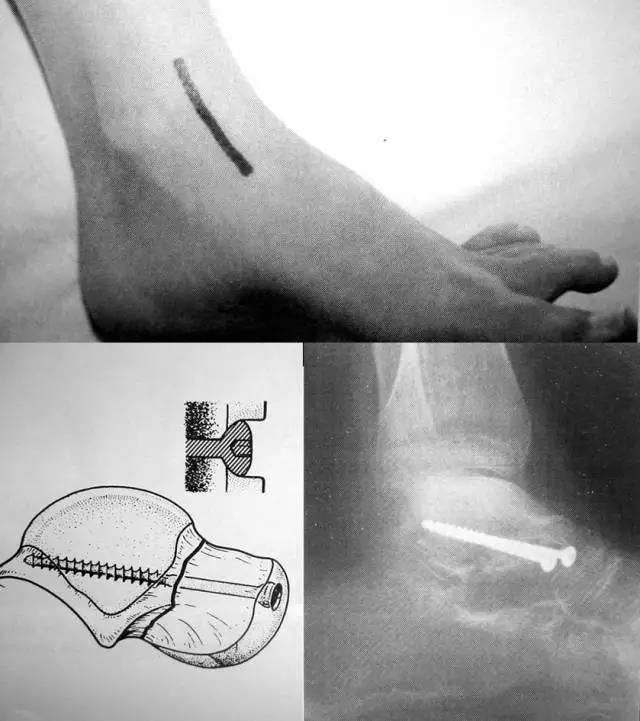

1前内侧入路

如距骨背侧、内侧粉碎严重,复位情况难以判断,可增加前外侧切口—跗骨窦上方延至第4跖骨基底能充分显露距下关节,仔细清除全部碎骨快并精确复位.

2前内入路+内踝截骨

3前外入路

4后外侧入路

长屈肌腱和腓骨肌肌腱间显露

后外侧入路的固定

5后内入路